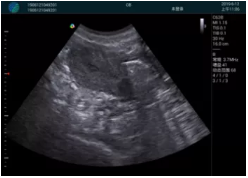

M20引導(dǎo)下,抽吸針找到右側(cè)宮角處再次清掃

二次抽吸后再次進(jìn)行超聲檢查,宮腔未見(jiàn)殘留,宮腔線(xiàn)清晰顯示